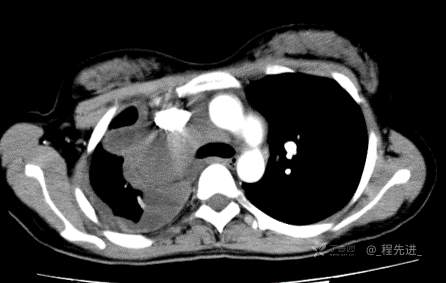

患者性别:女

患者年龄:26岁

简要病史:反复胸闷、气喘、咳嗽半年